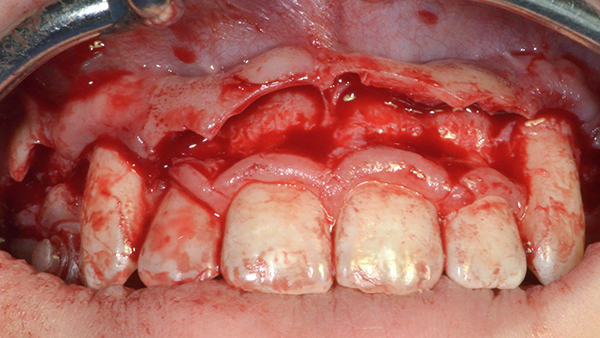

Diş tacının cərrahi uzadılması müxtəlif kliniki hallarda müxtəlif məqsədlərlə tətbiq edilən cərrahi müalicə prosedurudur. Bu metod estetik stomatologiyada “Gummy smile” (diş əti gülüşü) olaraq adlandırılan durumun ortadan qaldırılması məqsədilə geniş tətbiq olunur. Bu zaman kliniki hala bağlı olaraq bəzən yalnız diş əti, bəzən isə həm diş əti həm də sümükdən müəyyən miqdarda rezeksiya edilməklə (kəsilməklə) diş və diş ətinin estetik cəhətdən ideal görünüşü əldə olunur.